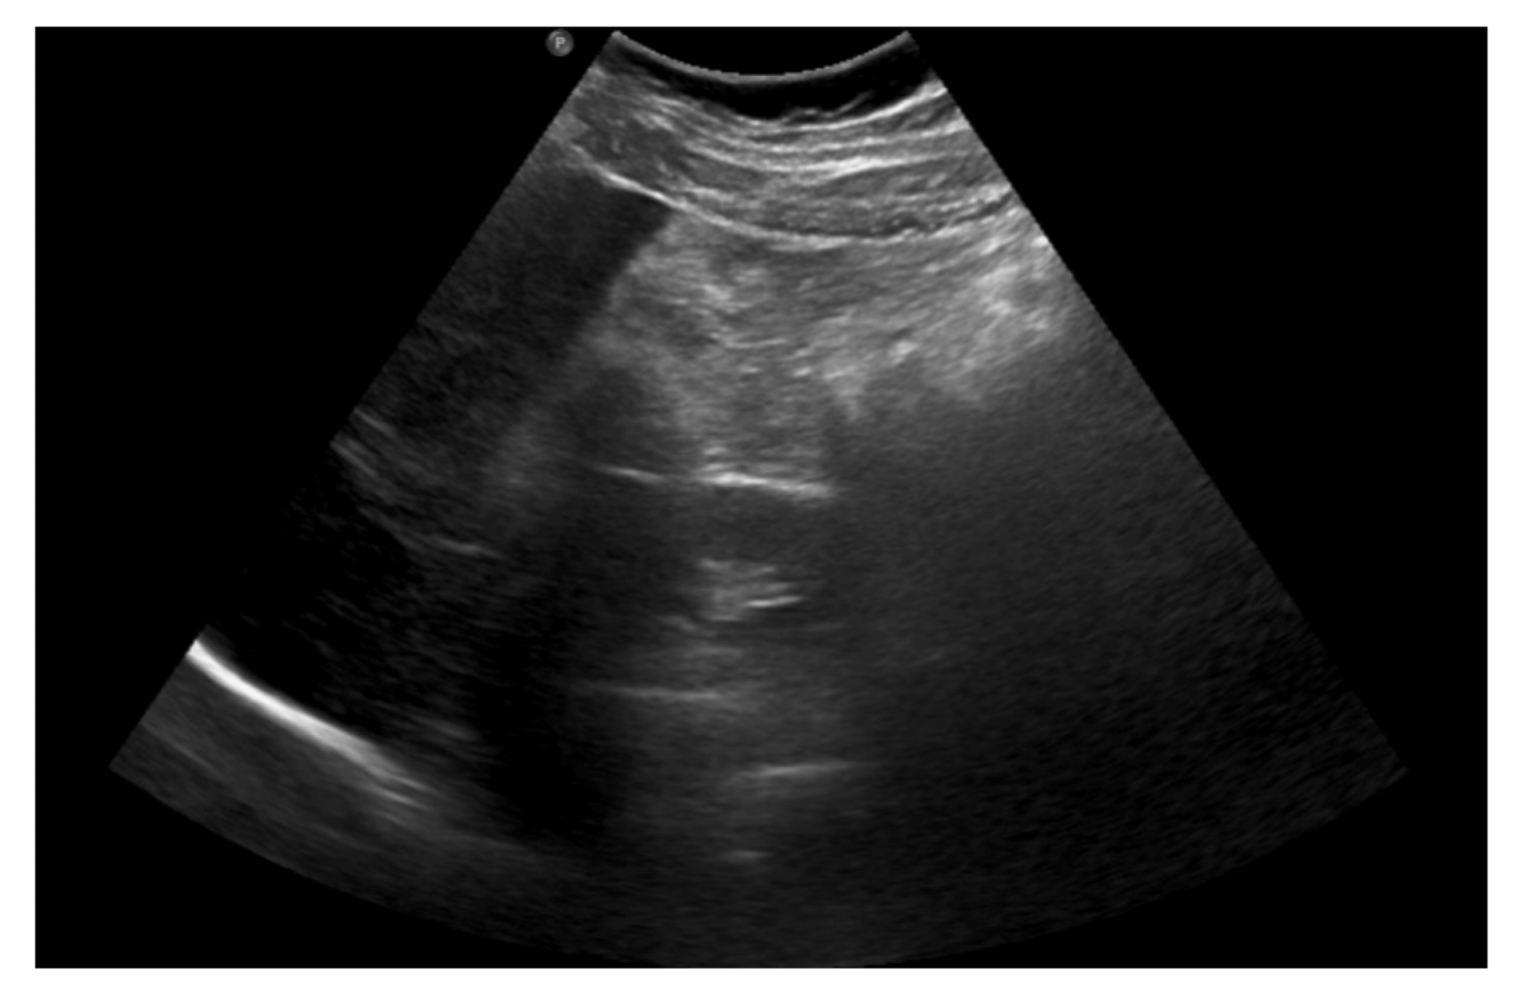

An abdominal ultrasound was then performed (Figure 2) and showed mesenteric adipose tissue along the right flank, with increased echogenicity. There was fluid in the pouch of Douglas, with a layer thickness of up to 25 mm, along with a trace of free fluid, both interloop and perihepatic. The appendix was not visualized, which prompted a further diagnostic work-up.

Figure 2. The abdominal ultrasound on admission: mesenteric adipose tissue with increased echogenicity and free fluid.